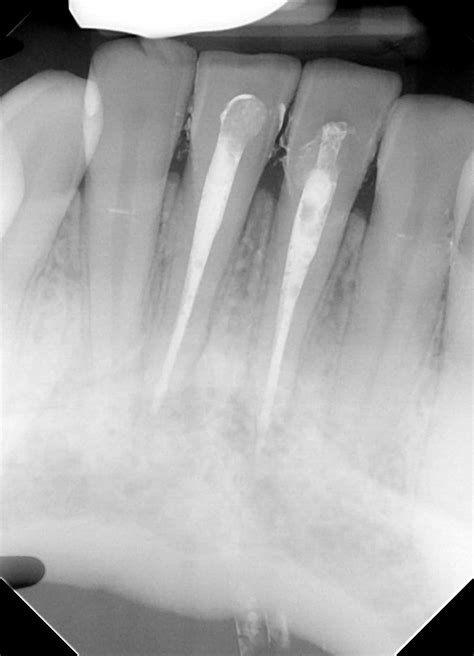

1. Diagnosis and Anesthesia: Your dentist will take X-rays to visualize the internal structure of the tooth. A local anesthetic is administered to ensure the area is completely numb.

2. Accessing the Pulp: A small hole is created on the back side of the front tooth to gain access to the pulp chamber. This keeps the front of the tooth intact for cosmetic purposes.

3. Cleaning and Shaping: The infected pulp is carefully removed using specialized instruments. The canal is then cleaned and shaped to prepare it for a filling material.

4. Filling and Sealing: The hollow canal is filled with a biocompatible material called gutta-percha. This seals the tooth to prevent bacteria from re-entering.